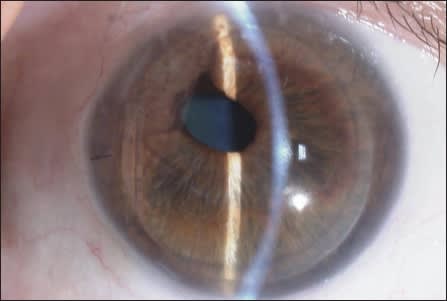

ICE syndrome is often unilateral, accompanied by glaucoma and typically occurs in younger patients. It may present with obvious iris distortion (essential iris atrophy), predominant cornea edema (Chandlers) or iris nodules (Cogan-Reese, Figure 4). Peripheral synechiae are usually present in all forms and thus account for the very high incidence of glaucoma.

Figure 4. Postop Cogan-Reese ICE after successful DSAEK.

The pathology is an abnormal transformation of the endothelial cells, with proliferation, not cell loss, almost like a down-growth picture. These sheets of abnormal cells are progressive and destructive. Corneal decompensation and glaucoma are the typical end result. The etiology of this condition is unknown, but a possible viral link has been theorized.